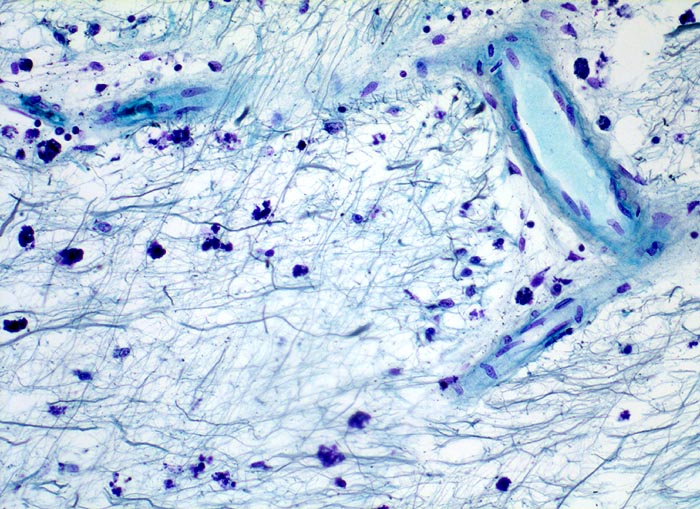

• Alter, scharf begrenzter Entmarkungsherd mit Verlust der blauen Myelinscheiden in der Holmes Luxol Färbung.

• Vollständiger Verlust der Markscheiden (fehlende blaue Farbe) bei erhaltenen Axonen (schwarze Fasern).

• Vereinzelte vorwiegend perivaskulär lokalisierte mononukleäre Entzündungszellen und mit Myelinbruchstücken beladene Makrophagen.